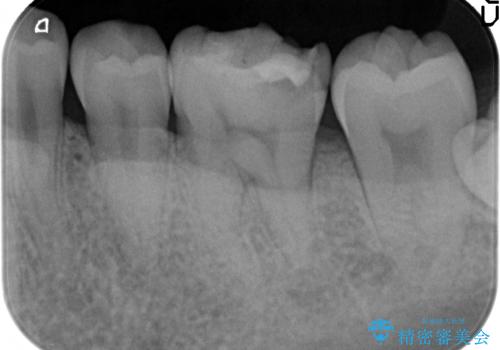

- 左下6の歯が欠けてしまったので診て欲しいといらっしゃった方の症例です。

虫歯除去後、オールセラミッククラウンによる補綴を行いました。